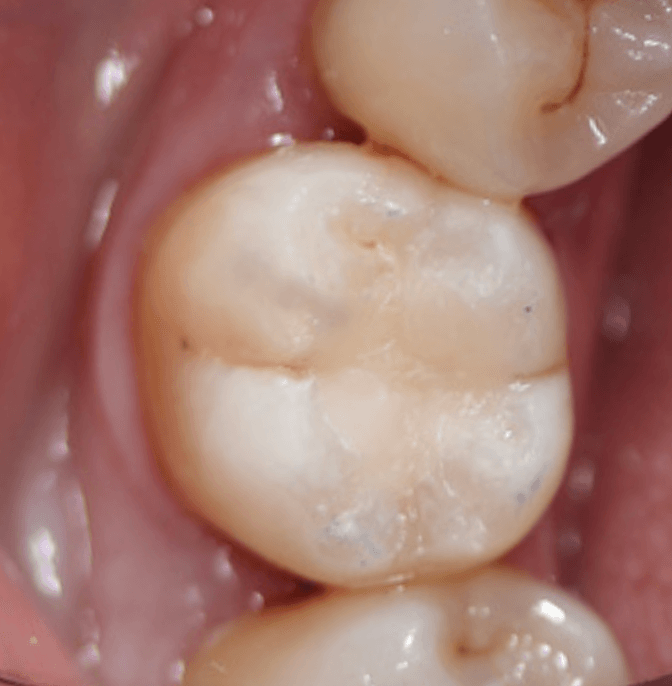

Case Study 3

This case involved a direct composite restoration to manage occlusal caries secondary to an existing GIC. Rubber dam isolation provided excellent moisture control and visibility, allowing for precise cavity preparation and layering technique. Upon reviewing the completed restoration in natural light as well as the photographs, a more accurate shade match would’ve been advantageous. The case reinforced the importance of good isolation for predictable bonding and also helped build my confidence in restoring posterior teeth with attention to anatomy and occlusion.

Case Study 2

This case involved a direct composite restoration to manage occlusal caries secondary to an existing GIC. Rubber dam isolation provided excellent moisture control and visibility, allowing for precise cavity preparation and layering technique. Upon reviewing the completed restoration in natural light as well as the photographs, a more accurate shade match would’ve been advantageous. The case reinforced the importance of good isolation for predictable bonding and also helped build my confidence in restoring posterior teeth with attention to anatomy and occlusion.

Case Study 1

These cases went smoothly from diagnosis to final restoration. I was pleased with the outcomes clinically and aesthetically, and the patients were very happy with the result. It was a rewarding reminder of how effective communication and attention to detail can lead to a positive experience for both patient and operator.